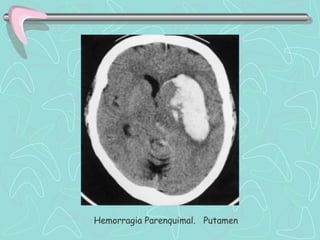

DIAGNÓSTICO

TOMOGRAFÍA COMPUTARIZADA DE ENCÉFALO

•Examen de elección en el Ictus agudo

ICTUS HEMORRÁGICO

•Lesión Hiperdensa que ocupa espacio y desplaza en

diverso grado el parénquima cerebral.

•En HSA puede ser poco hiperdensa, de ubicación

extraparenquimal, e invadir ventrículos cerebrales.

Las Neuroimágenes informan sobre el tipo de lesión, su

tamaño, localización, distribución vascular; la presencia de

complicaciones, y también sobre la necesidad de manejo

quirúrgico.

Hemorragia Parenquimal. Putamen